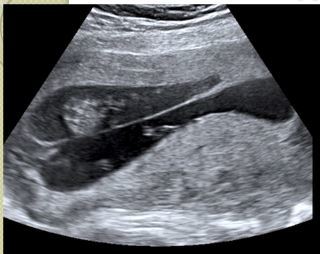

What is this?

Multiple Gestation

• US of intertwin membrane showing “Lambda Sign” = Dichorionic twins

• Fraternal Twins (Dizygotic)

• Diamniotic = 2 amniotic sacs